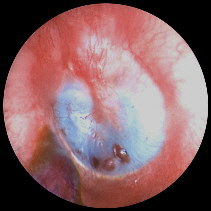

Figure 4. Material excised from posterior and inferior tympanum Click image for full size view.

The anterior tympanum was still filled with the rubber material This was not able to be

retrieved deep to the malleus. Further extension of the incision anteriorly

allowed the drum to be retracted posteriorly and the remainder of the silicon

was able to be removed in this fashion.

Figure 5. Material has been removed from anterior tympanum and Eustachian tube. Click image for full size view.

There was an extension which appears to

have gone down into the eustachian tube which came out as a single large piece.

Impression material cast of the Eustachian tube, removed intact.